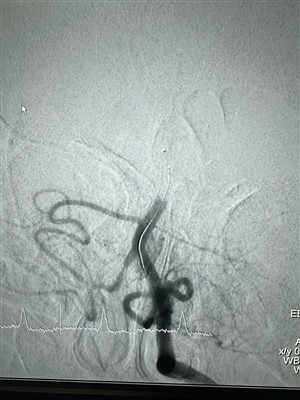

LAVA Liquid Embolic System -käyttötapauksetJaa äskettäinen interventioleikkaus, joka suoritettiin NeuroSafen LAVA Liquid Embolic System -järjestelmällä.

Enemmän -

Tapaus, jossa käytetään LAVA Liquid Embolic System -järjestelmää Espanjassa64-vuotias miespotilas, jolla on infrarenaalinen AAA (enimmäishalkaisija 79 mm), repeytynyt ja hoidettu EVAR:lla. CT-angiografiakontrollissa vuotta myöhemmin, aneurysmapussin (enimmäishalkaisija 84...